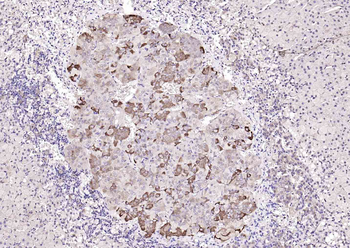

RARB Rabbit Polyclonal Antibody [orb11327]

FC, ICC, IF, IHC-Fr, IHC-P, WB

Bovine, Canine, Gallus, Porcine, Rat

Human, Mouse

Rabbit

Polyclonal

Unconjugated

50 μl, 100 μl, 200 μlTIG2 Rabbit Polyclonal Antibody [orb11481]